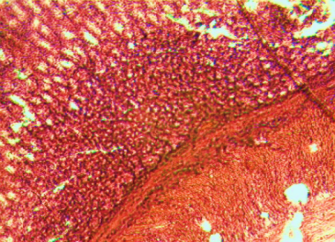

Histological evaluation of gastric lesion

Histological observation showed extensive damage of the gastric mucosa in the ulcer negative control group with necrotic lesions penetrating deeply into the mucosa accompanied by extensive edema and leucocyte infiltration of the submucosal layer (group 2).

Rats that received treatment with aqueous and methanol extracts of the leaves of D. thollonii had comparatively better protection of the gastric mucosa as seen by the reduction of ulcer area, reduced submucosal edema and leucocytes infiltration after 14 days of treatment (fig. 4).

Fig. 4: Histological study of acetic acid-induced gastric damage in rats

In fig. 4: (a’): histological section of a normal control rat: no injuries to the gastric mucosa are seen and the gastric wall is normal. ((b’): histological section of an ulcer negative control rat: there is severe destruction of the surface epithelium and necrotic lesions penetrating deeply into mucosa and submucosa layer. (c’): histological section of rats treated with Maalox (50 mg/kg): the gastric wall appears normally, but there is edema of mucosa and sub mucosa layer.(d’): the histological section of rats treated with Ranitidine (50 mg/kg): the gastric wall appears normally with all layers. (e’): the histological section of rats treated with 125 mg/kg of aqueous extract: there is mild disruption of the sub mucosal layer. (f’): histological section of rats treated with 250 mg/kg aqueous extract: there is moderate disruption of the surface epithelium. (g’): histological section of rats treated with 500 mg/kg of aqueous extract: there is mild disruption of the sub mucosal layer and edema of the muscle. (h’): histological section of rats treated with 125 mg/kg of methanol extracts: there is mild disruption of the epithelium surface and the sub mucosal layer and edema of the serosal layer. (i’): histological section of rats treated with 250 mg/kg of methanol extract: there is mild disruption of the epithelium surface and edema of the submucosal and serosal layers. (j’): histological section of rats treated with 500 mg/kg of methanol extract: there is moderate disruption of the epithelial surface although the gastric wall appears normally.